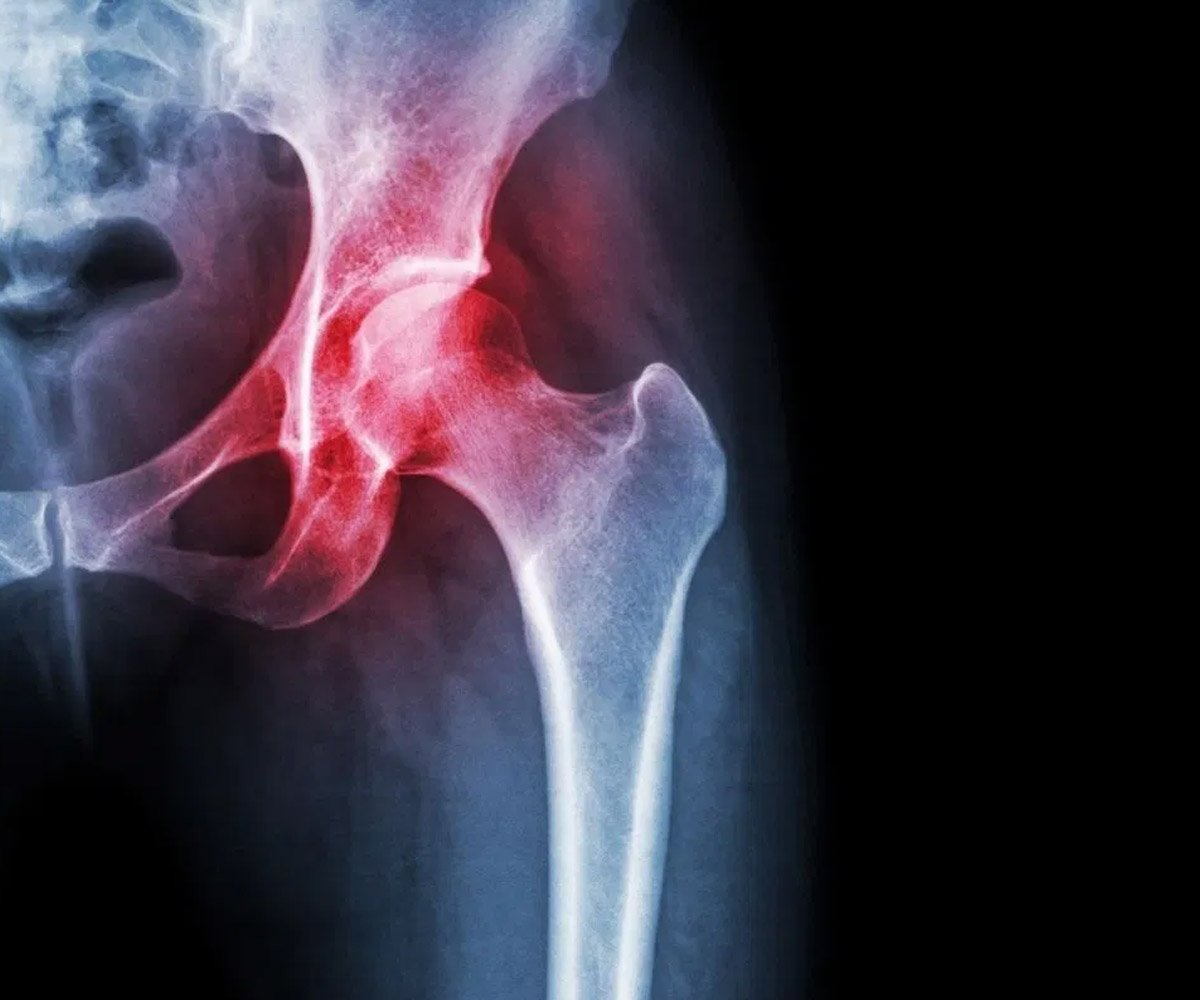

As radiografias em diversas posições são imprescindíveis para o entendimento da geometria da bacia, e o diagnostico de alterações ósseas que possam provocar lesões como impacto femoro acetabular, displasias, além de afastar outras enfermidades ósseas.